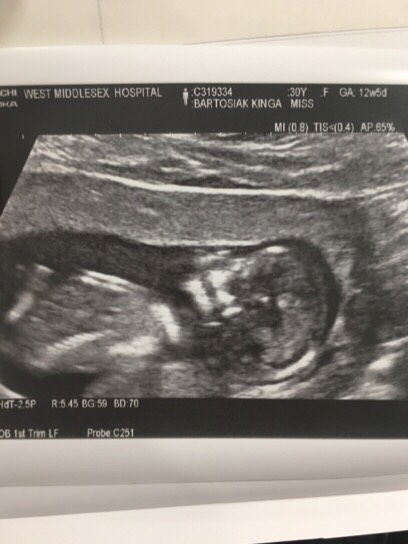

Dzisiaj wizyta mam nadzieję, że wszystko jest w porządku. Chciałabym już w końcu znać płeć dzidziusia by móc coś ładnego kupić :-]